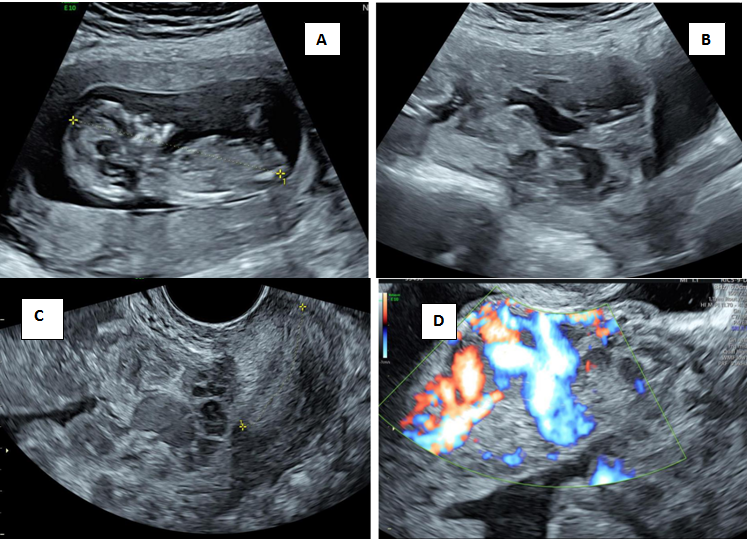

Figure 2 is an illustration of cervical pregnancy .On ultrasound the gestational sac is present in the cervix (Figure 2A), an intact part of cervical canal exists between the sac and the closed internal os (Figure 2B) with peritrophoblastic flow (Figure 2C).14,15 3D ultrasound depicts the typical hour glass appearance of cervix. (Figure 2D) A mere presence of sac in the cervix could also indicate the cervical stage of abortion, and can be differentiated by demonstration of sliding sign on ultrasound.2

Figure 2 Cervical pregnancy (CP)

A) Transabdominal ultrasound shows the gestational sac within the cervix and empty uterine cavity B) Transvaginal ultrasound shows the gestational sac within the cervix with an intact part of cervical canal existing between the sac and the closed internal os (arrow) C) Peritrophoblastic flow surrounding the sac. D) 3D ultrasound showing hour glass appearance with closed internal and external os.